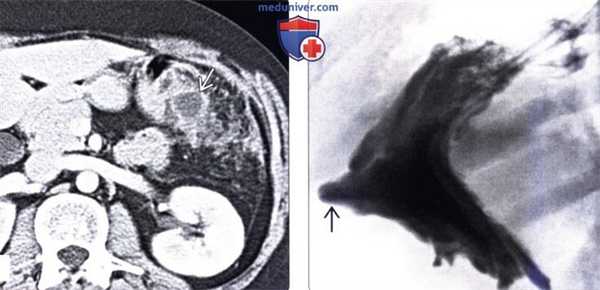

(Слева) На КТ с контрастным усилением, выполненной по поводу пенетрирующей язвы желудка, определяются выбухающие складки вдоль большой кривизны и воспалительные изменения в прилежащей брыжеечной клетчатке. Обратите внимание на отграниченное скопление жидкости, тесно прилежащее к желудку.

(Справа) На рентгенограмме в боковой проекции, выполненной во время рентгеноскопии желудка у этого же пациента, визуализируются утолщенные складки желудка и язва, проецирующаяся за пределами контура желудка по большой кривизне. Расположение язвы соотносится с локализацией жидкости и воспалительных изменений, обнаруженных на КТ.